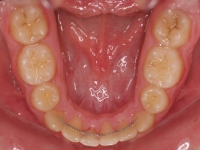

La paciente O.O. acude a nuestra consulta por:

– Canino 13 e incisivo lateral 42 en posición ectópica.

– Canino 23 incluido.

Con lo que decide realizarse un tratamiento de ortodoncia de duración de 24 meses con brackets damon Q.

CASO COMPLETO: